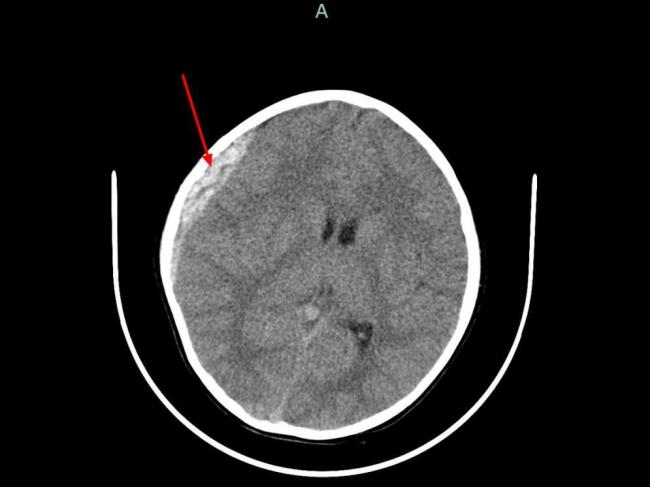

浙大儿院急诊科主任吴秀静表示,近一个多月已收到5例溺水患儿,其中一对兄妹因在家门口小河边玩水不慎失足溺亡。吴秀静建议家长全程监护,远离危险水域,不要让孩子独自或结伴在河边、池塘、水库等水域玩耍;带孩子游泳时选择正规场所,全程陪伴,避免分散注意力的行为。她还强调了“六不准”原则:不私自下水游泳,不擅自与他人结伴游泳,不在无家长或教师带领的情况下游泳,不到无安全设施、无救援人员的水域游泳,不到不熟悉的水域游泳,不盲目下水施救。